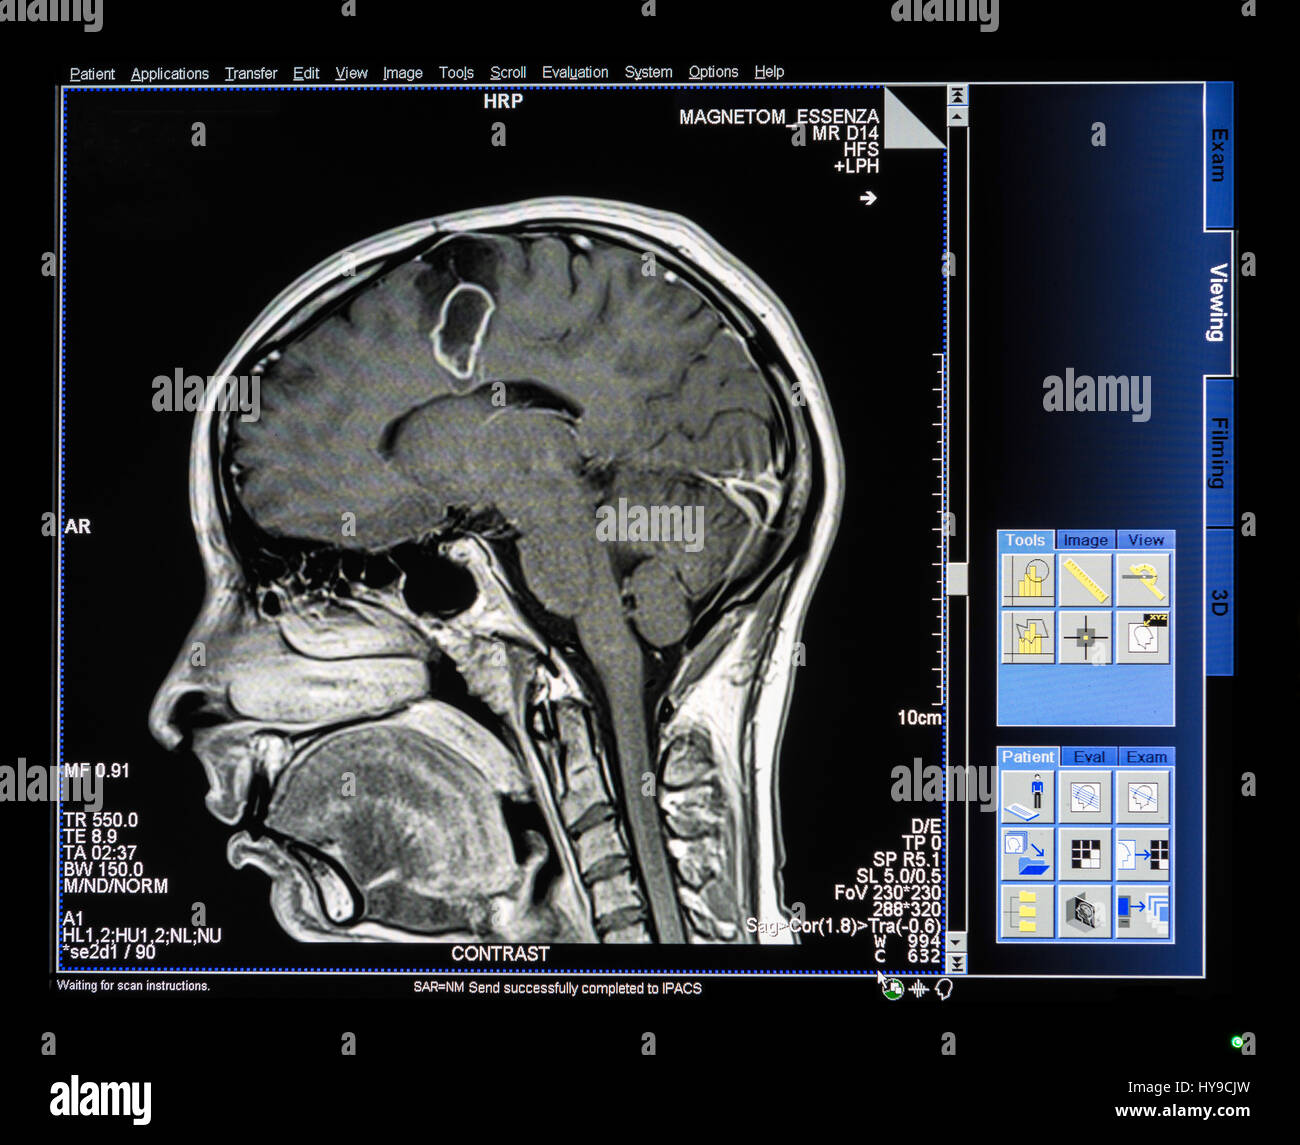

Engineer Team : RESONANCIA MAGNETICA Magnetic Resonance Imaging – Clinical Images Hallazgos por resonancia magnética cerebral de nuestro paciente. M, 21 … Imágenes por resonancia magnética anormales como predictoras de mal … Imágenes por resonancia magnética anormales como predictoras de mal … Lesiones en resonancia magnética (RM) del encéfalo y la médula espinal … Pin en Resonancia Magnética del Encéfalo A) Resonancia magnética cerebral (RMC) mostrando infartos en … Caso 1: Edema cerebral visualizado mediante RM. (A) Secuencia T1 plano … Rascacielos dormir pasta tac y resonancia diferencias retrasar … Pin on Apuntes de Enfermería y T.C.A.E Resonancia magnética cerebral secuencia T2, que muestra lesión … Meningitis aguda en la enfermedad de Behçet | Reumatología Clínica Resonancia magnética coronal normal del cerebro Fotografía de stock – Alamy Imágenes de resonancia magnética, la imagen de la cabeza en diferentes … Resonancia magnética cerebral A) protocolo T1 sagital (Caso 1). Se … Resonancia magnética cerebral. Secuencia T1 corte sagital. Atrofia … Resonancia magnética de cerebro, cortes axiales, secuencias T2. Señal … Resonancia magnética de cráneo. A y B) Cortes axiales FLAIR … Resonancia magnética (RM) de cerebro, corte axial ponderado en T2: la … RM cerebral: Interpretación paso a paso | Kenhub Resonancia magnética de cerebro, cortes axiales, secuencias T2. Señal … De Resonancia Magnética De Cerebro Foto de archivo – Imagen de arteria … Top 107+ Imagenes de resonancia cerebral normal – Destinomexico.mx -Imagen por resonancia magnética del cerebro. a) Cortes sagital y axial … resonanCia magnétiCa Cerebral donde se observa hiperintensidad a nivel … MRI (Imagen de resonancia magnética) – Tomografía computarizada de la … Meningioma – NCI Imágenes por resonancia magnética coloreadas del cerebro sano del … Resonancia magnética cerebral en secuencia FLAIR, que muestra lesiones … Contraste resonancia magnetica cerebral – senturinthegreen Relación de los espacios de Virchow-Robin con la enfermedad de … Gliomatosis cerebral – Instituto Nacional del Cáncer Pin en Neurology. Recomendaciones para la utilización e interpretación de los estudios de … Fotografía De La Proyección De Imagen De Resonancia Magnética Del … atmósfera Dirigir Cumplir anatomia resonancia magnetica Desarrollar … Pin en #MEDICINA,#SALUD Resonancia magnética de la nasofaringe De Resonancia Magnética De Cerebro Foto de archivo – Imagen de polilla … Atrofia cortical global de predominio parietal en la Resonancia … Resonancia magnética cerebral | Download Scientific Diagram Neuroblog: Resonancia magnética cerebral en la trombosis crónica de … De Resonancia Magnética De Cerebro Imagen de archivo – Imagen de … ¿Cuáles son los riesgos de la resonancia magnética? – Integra Salud … Resonancia magnética cerebral al decimocuarto día de ingreso: área … Resonancia magnética. Corte axial mostrando área infartada en el … Resonancia magnética cerebral del paciente AV evidenciando lesiones en … -Ressonância magnética de encéfalo mostrando múltiplas imagens … Resonancia magnética cerebral secuencia FLAIR (Fluid Attenuated … Resonancia magnética cerebral con protocolo de epilepsia, en sección … Resonancia magnética cerebral en corte sagital. Se observa una evidente … Resonancia magnética craneal en la que se evidencian lesiones … Logran visualizar el cerebro a detalle más completo tras una resonancia … Así decide el cerebro la severidad de un castigo De Resonancia Magnética De Cerebro, Imagen de archivo – Imagen de … A) Resonancia magnética cerebral; Secuencia Tof: oclusión de arteria … Un estudio asocia la ansiedad con la aparición rápida del Alzheimer IMÁGENES DE 18 F-PR04.MZ PET FUSIONADA CON RESONANCIA MAGNÉTICA … Imágenes por resonancia magnética anormales como predictoras de mal … Tumores de la región pineal – Instituto Nacional del Cáncer Epilepsia: una historia de voces y fantasmas | Neurología Contribución de las imágenes de resonancia magnética por tensor de … Resonancia magnética secuencia T2 plano coronal de quiste epidermoide … Resonancia Magnética Cerebral del paciente: a. Aumento de… | Download … Resonancia magnética cerebral 2022 Síndrome de hemiconvulsión-hemiplejía-epilepsia. Seguimiento de un caso … Enfoque Radiologico: La resonancia magnética permite detectar lesiones … Resonancia magnética craneal T1 con contraste que muestra angiomatosis … guidewiz – Blog Resonancia magnética cerebral, secuencia SWI. Ribete hipointenso en la … resonAnCiA mAgnétiCA de ColumnA Con gAdolinio. Corte sAgitAl en t1 de … SEMANA 12: FUNDAMENTOS DE RESONANCIA MAGNÉTICA NUCLEAR. INDICACIONES Y … DIAGNÓSTICO DE ESCLEROSIS MÚLTIP Magnetic resonance imaging of the brain – Alchetron, the free social … Resonancia magnética de órbitas | Instituto Radiológico Dr. E Castillo Alteración de la marcha en un paciente post-trasplante hepático Resonancia magnética cerebral de un paciente sano (Ay B) y paciente que … Utilidad de la resonancia magnética craneal para el diagnóstico de la … Resonancia Magnética Del Cerebro El Tumor Cerebral Foto de stock y más … De Resonancia Magnética De Cerebro Imagen de archivo – Imagen de … ABDALLA RADIOLOGIA: NEURINOMA ACUSTICO Atrofia cortical global de predominio parietal en la Resonancia … Resonancia Magnética : Producción de la imagen MRI Brain Scan — Stock Photo © Bunyos30 #18724051 Mri (imagen de resonancia magnética) Monitor con imagen de captura de … Tomografía computarizada vs resonancia magnética: diferencia y … Tumores Cerebrales – Unidad de Neurocirugía RGS Resonancia magnética de la columna, sección sagital. Observe los discos … La resonancia magnética, una técnica imprescindible en el diagnóstico … Perfusión Cerebral por Resonancia Magnética | ¿Qué es? ¿Necesita Contraste? Resonancia Magnética Cerebro A: resonancia magnética, T2 coronal preoperatoria; se observa lesión en … Resonancia magnética cerebral — Foto de stock © Bunyos30 #27340623 La resonancia magnética se perfila como detector de mentiras | Futuro … Resonancia magnética cerebral en T1 con gadolinio, cortes axial (a … MRI brain : show brain tumor at right parietal lobe of cerebrum — Stock … NEUROIMÁGENES EN ENFERMEDAD DE PARKINSON: ROL DE LA RESONANCIA …